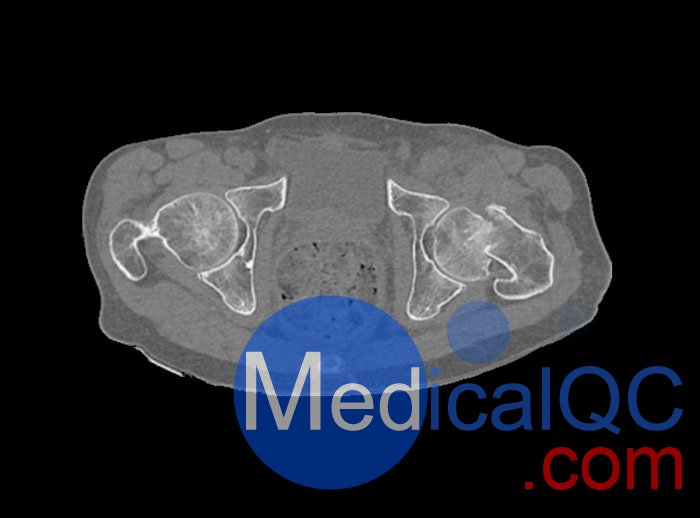

WEK54-01股骨頸骨折骨盆模型,WEK54-01骨盆模體模擬沒有靜脈造影劑的骨盆(天然)。它覆蓋了整個骨盆,直到第五腰椎。

左側(cè)股骨頸移位骨折。

該模型可用于 CT(包括 CBCT)和射線照相,以評估和優(yōu)化成像性能和后處理應(yīng)用,包括支持 AI 的應(yīng)用。它也適用于培訓(xùn)目的。

骨骼和軟組織的逼真模擬。